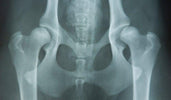

Hip dysplasia is a hereditary condition in which the hip socket and ball do not fit together properly. This results in an unstable joint that can cause wear and tear and pain over time. Although it mainly occurs in large dog breeds such as the German Shepherd, Labrador Retriever and Golden Retriever, smaller dog breeds can also be affected.

Photo by: licg